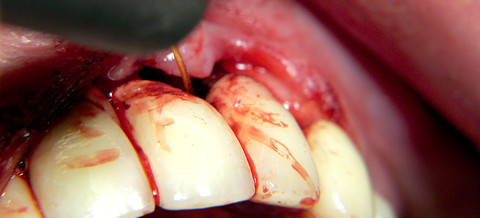

Typische Anwendung eines Diodenlasers – die Therapie der Periimplantitis. Abb. 1: Bleeding on Probing an einem vor sechs Jahren incorporierten Implantat in der Oberkieferfront. Abb. 2: Auch das Röntgenbild zeigt typische Manifestationen einer Periimplantitis, einen kraterförmigen Knocheneinbruch.

Abb. 3: Bei der Mobilisation der Weichteile wird das ganze Ausmaß der knöchernen Destruktion sichtbar. Abb. 4: Diodenlaserdekontamination: unter Kontakt der Faser zur freiliegenden Implantatoberfläche mit einer Leistung von 1 Watt im cw-mode wird das Laserlicht maximal 20 Sekunden appliziert. Abb. 5: Postoperativer Nahtverschluss.